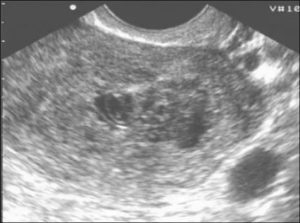

Для уточнения патологии проводится ультразвуковое исследование, на снимке визуализируются отдельные компоненты зародыша или кровяные сгустки. На развитие воспалительного процесса указывает повышенное содержание лейкоцитов при сдачи анализа мазка или крови.

Гинеколог выявляет мягкую консистенцию органа при осмотре. Подтверждают развившийся негативный процесс клинические и биохимические анализы мочи и крови, трансвагинальное УЗИ (ультразвуковое исследование).

Проводится визуальный осмотр шейки матки и пальпация. Внутренний зев ее будет расширен, плодный остаток в наличии. УЗИ определит его объем и локализацию, а также общее состояние репродуктивных органов. Биохимический анализ крови расскажет о функционировании органов и систем пациентки.